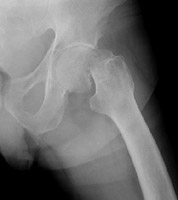

- Click on the image for a larger versionAAP radiograph of the left hip. This shows an incomplete fracture of the femoral head, Garden I in staging.